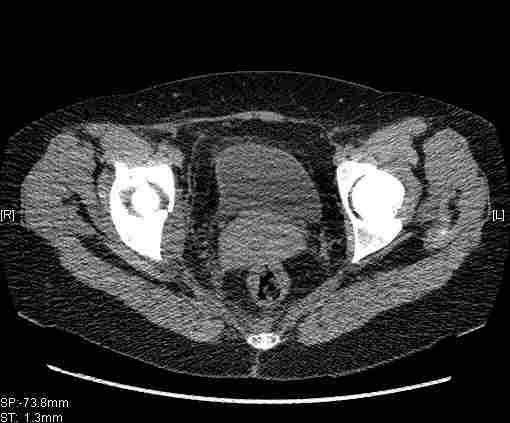

Женщина,58 лет, после ДТП 6 суток. Первично повреждение расценено как переломы ветвей лонной кости. После подтверждения повреждения вертлужной впадины,как чаще всего случается, вопрос встал о тактике. БОльшинство за консерватиное лечение.К сожалению кт у нас "во время" сломался. Прилагаю стандартные снимки вертлужки. У меня следующие вопросы к коллегам:1. Правильно ли рассценивать это повреждение как Т-образный перелом вертлужнй впадины?2. Можно ли добиться анатомической репозиции поверхности вертлужной впадины скелетным вытяжением в данном случае, если нет, что будет этому препятствовать?3. Если смещение останется таким как сейчас, через какое время появится необходимость эндопротезирования (по вашему опыту)?Спасибо.

Удалось сегодня вывести пациентку в соседнюю больницу, где есть кт. Срезы сделаны только горизонтальные.

|